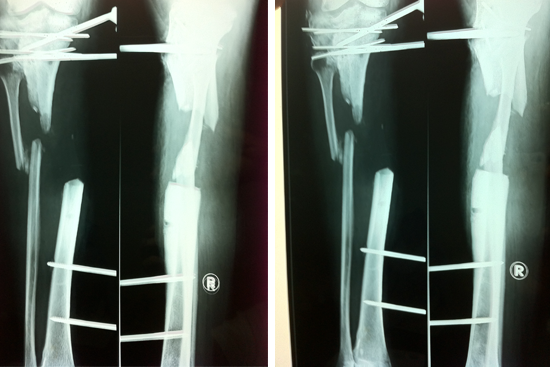

Tibialisation Of Fibula